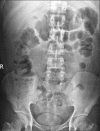

Figures